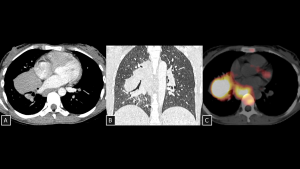

Fig 12: Case 13 – Ectopic parathyroid gland:

Panels A, B, and C demonstrate an elongated, well-defined solid nodule posterior to the esophageal wall (visceral mediastinum) (arrows in A and B), with apparent arterial supply originating near the thyroid gland. This lesion was identified as a hyperfunctioning ectopic parathyroid gland on technetium-99m sestamibi scintigraphy (C).

SYSTEMATIC APPROACH: 1. Age: Adults. | 2. Morphology: Oval nodule. | 3. Enhancement: Avid enhancement (Wash-in/Wash-out). | 4. Relevant Anatomical Relationships: Visceral compartment (along the migration pathway of the glands).

Fig 13: Case 14 – Cardiac Lymphoma:

Axial (A) and coronal (B) CT Coronary Angiography reveal hypoattenuating soft-tissue lesions encasing the cardiac chambers. Volume Rendering reconstructions (C and D) provide a 3D perspective of the tumor burden, clearly depicting the relationship between the masses and the heart chambers.

SYSTEMATIC APPROACH: 1. Age: Immunocompromised or Elderly. | 2. Morphology: Infiltrative, homogeneous soft-tissue mass. | 3. Enhancement: Mild to moderate (Homogeneous). | 4. Relevant Anatomical Relationships: Right Atrium and pericardium; encases coronary vessels.